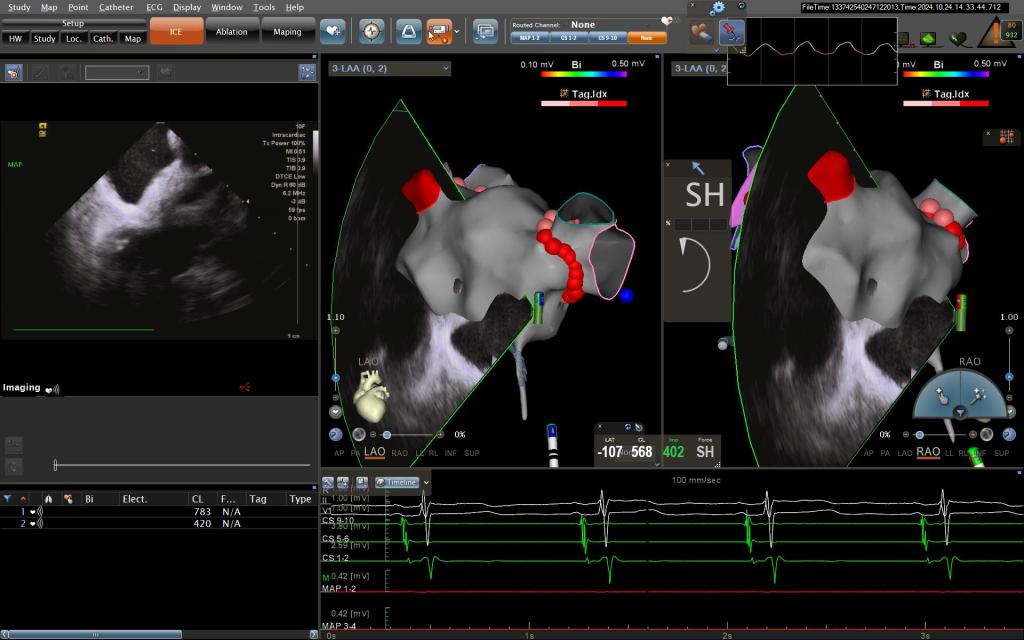

手术过程中,王洪涛教授亲自操刀,充分利用CARTO 3三维标测系统,实现了精准定位和消融,成功为患者实施了房颤射频消融术。随后,团队又克服了镜面右位心带来的操作困难,使用新一代国产左心耳封堵器LACbes成功完成了左心耳封堵术,有效预防了卒中的发生。王洪涛教授解释:“房颤射频消融术能够消除房颤的症状,而左心耳封堵术则能够闭合房颤患者血栓发生的根源部位,两者结合能够大大降低患者的卒中和出血风险。”

房颤是一种常见的心律失常疾病,其最大的危害在于形成血栓导致脑中风。对于镜面右位心合并房颤的患者来说,传统治疗方法往往难以兼顾抗凝和减少出血风险的需求。此次房颤射频消融联合左心耳封堵一站式手术的成功实施,为患者提供了一种全新的治疗选择。